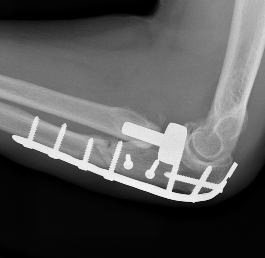

ORIF olecranon with plate +/- LCL repair

- posterior approach and plate olecranon

Olecranon plate + ORIF Type II coronoid process + radial head replacement

Olecranon plate with radial head replacement

Olecranon plate with radial head replacement + LCL repair

Olecranon plate + medial coronoid buttress plate + radial head replacement